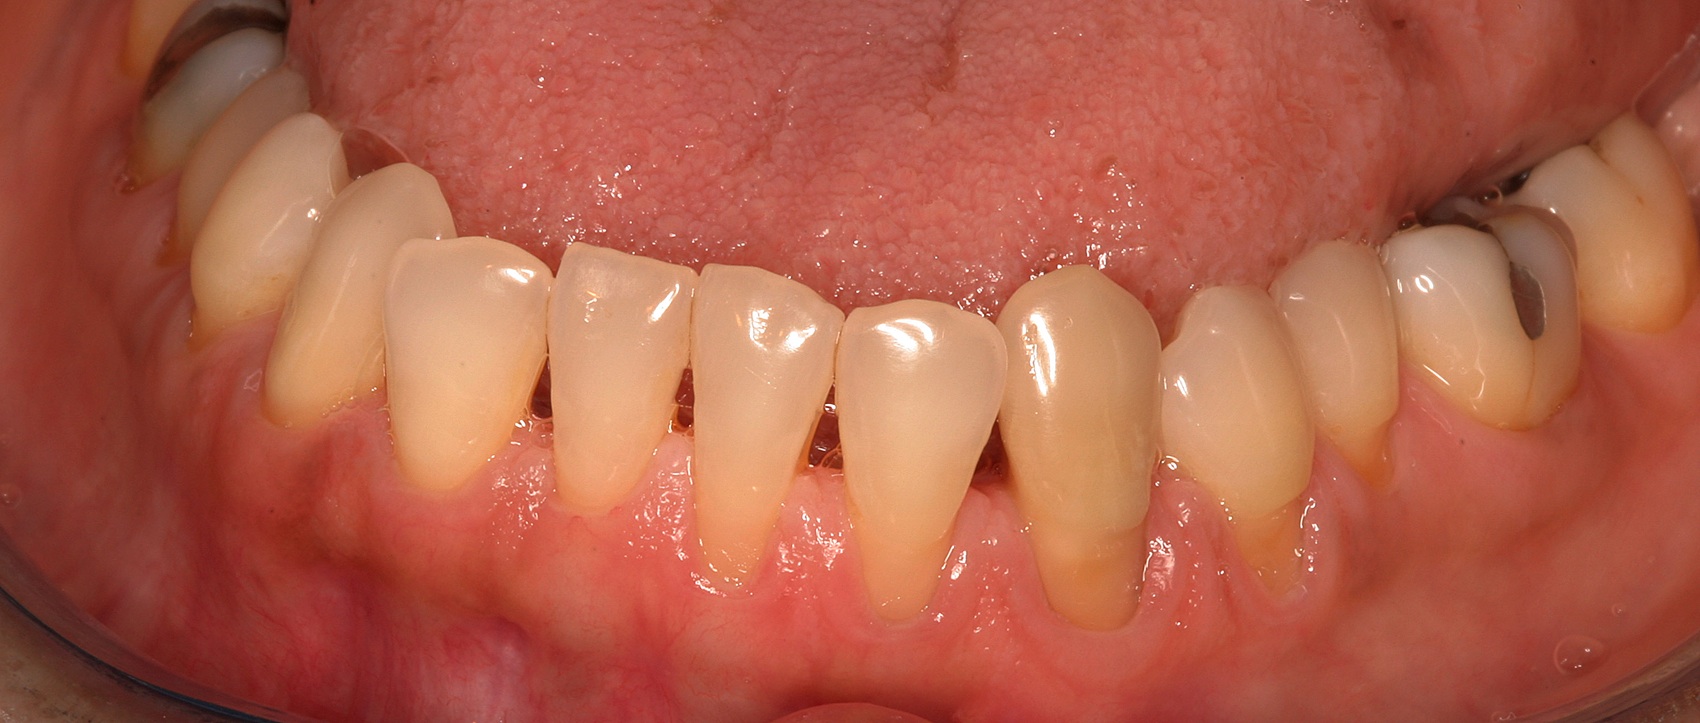

Facial bone loss and a mesial vertical defect.

Fig. 3

Then, too, are opportunities to prepare the site for regeneration by coupling therapies, applying an enamel matrix derivative, along with traditional bone grafts of demineralized freeze-dried bone allograft; potentially, gains in attachment with minimal probing depth and retained papilla may avoid the need for an implant (Figure 2 through Figure 7).